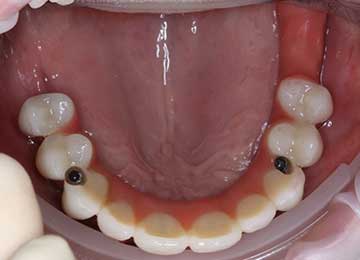

Имплантация зубов: фото "До" и "После"

Фото ДО

Фото ПОСЛЕ

Наведите для просмотра

All-on-4